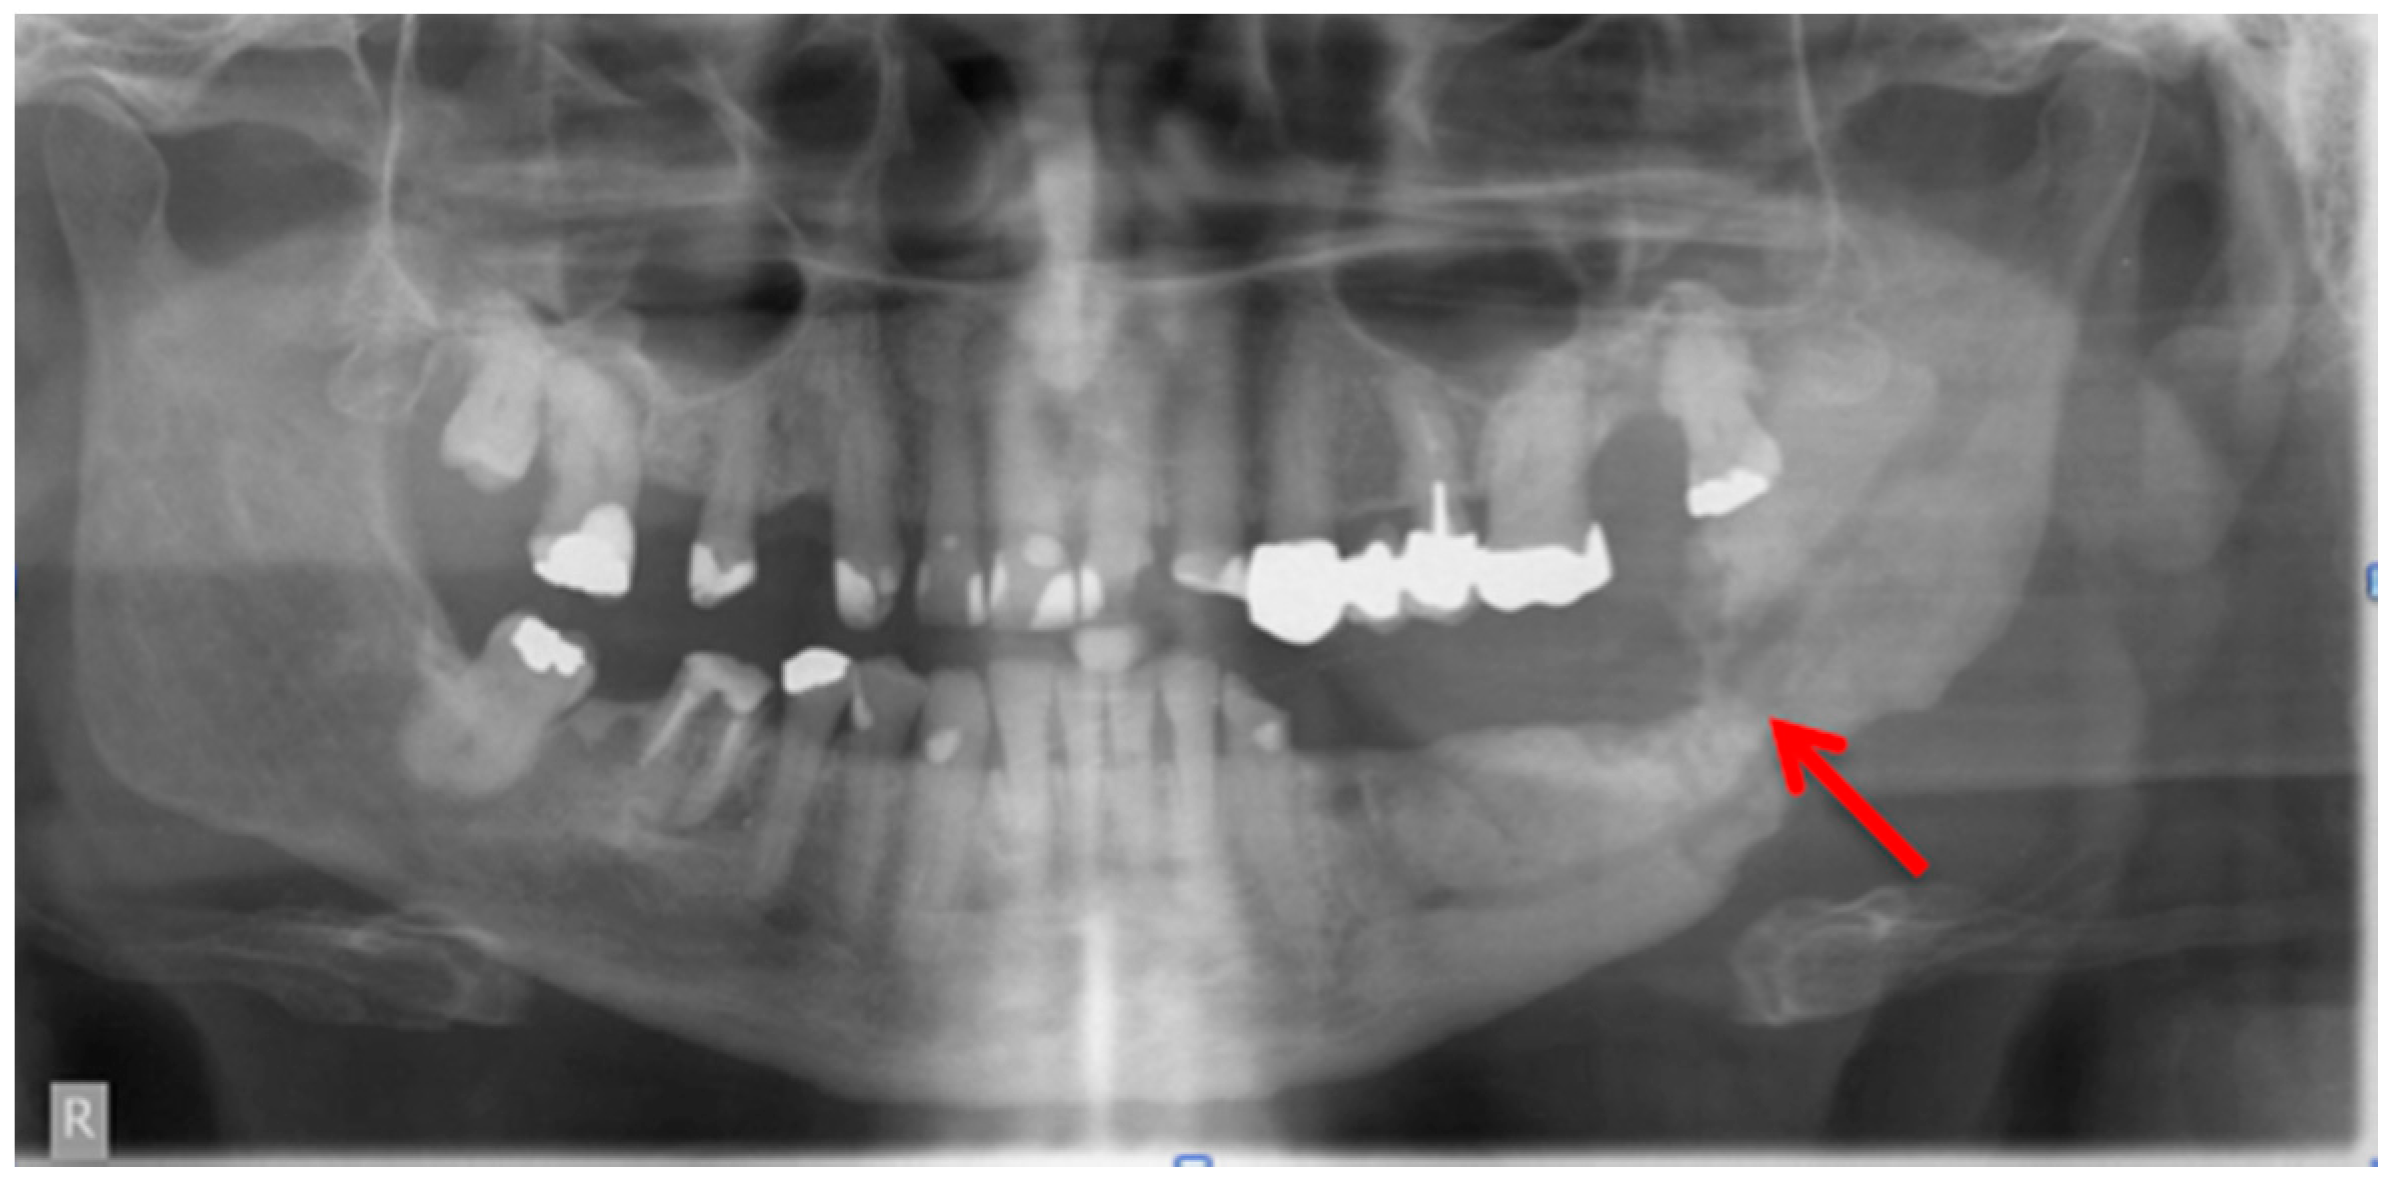

Figure 3.

Panoramic radiograph: Patient: 66 years old, male, secondary osteoporosis due to castration, alendronate. Red arrow indicates the almost invisible fracture. The computed tomography (CT) scan is shown in Figure 6 and the corresponding single photon emission computed tomography (SPECT) and SPECT/CT images in Figure 8 and Figure 9 respectively. AAMOS staging: stage 3.

Bianchi et al. [20] assessed 32 panoramic radiographs and CT scans in detail for the following features: “structural alteration of trabecular bone, from initial change in thickness and mineral content of the trabeculae to the formation of microlacunae; cortical bone erosion; osteosclerosis; small (less than 15 mm) sequestrum; extensive (more than 15 mm) sequestrum; and presence of periosteal new bone.” They found that CT was superior to dental panoramic radiographs in detecting all the radiologic signs [20]. Cortical bone erosion and trabecular bone resorption were visible to different extents. In their readings they found that panoramic radiographs missed the correct diagnosis of sequestra in 15 cases [20]. In our example case, even a fracture could be missed if only the panoramic radiograph is assessed (Figure 3 and Figure 5).

Figure 5.

Computed tomography (Siemens, Sensation 64) Patient: 66 years old, male, secondary osteoporosis due to castration, alendronate. Red arrow points in the direction of the fracture due to the bisphosphonate necrosis. The panoramic radiograph is shown in Figure 3 and the 99Tcm-DPD SPECT and 99Tcm-DPD SPECT/CT in Figure 8 and Figure 9 respectively. AAMOS staging: stage 3.